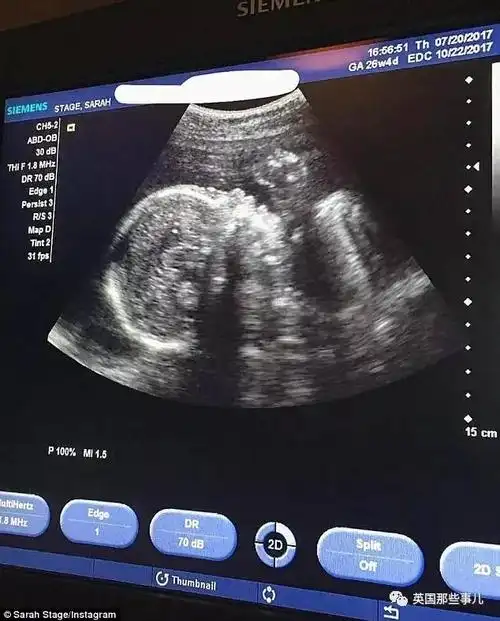

"甚至有网友压根就不相信她怀孕了…还有些网友表示:六个月肚子还保